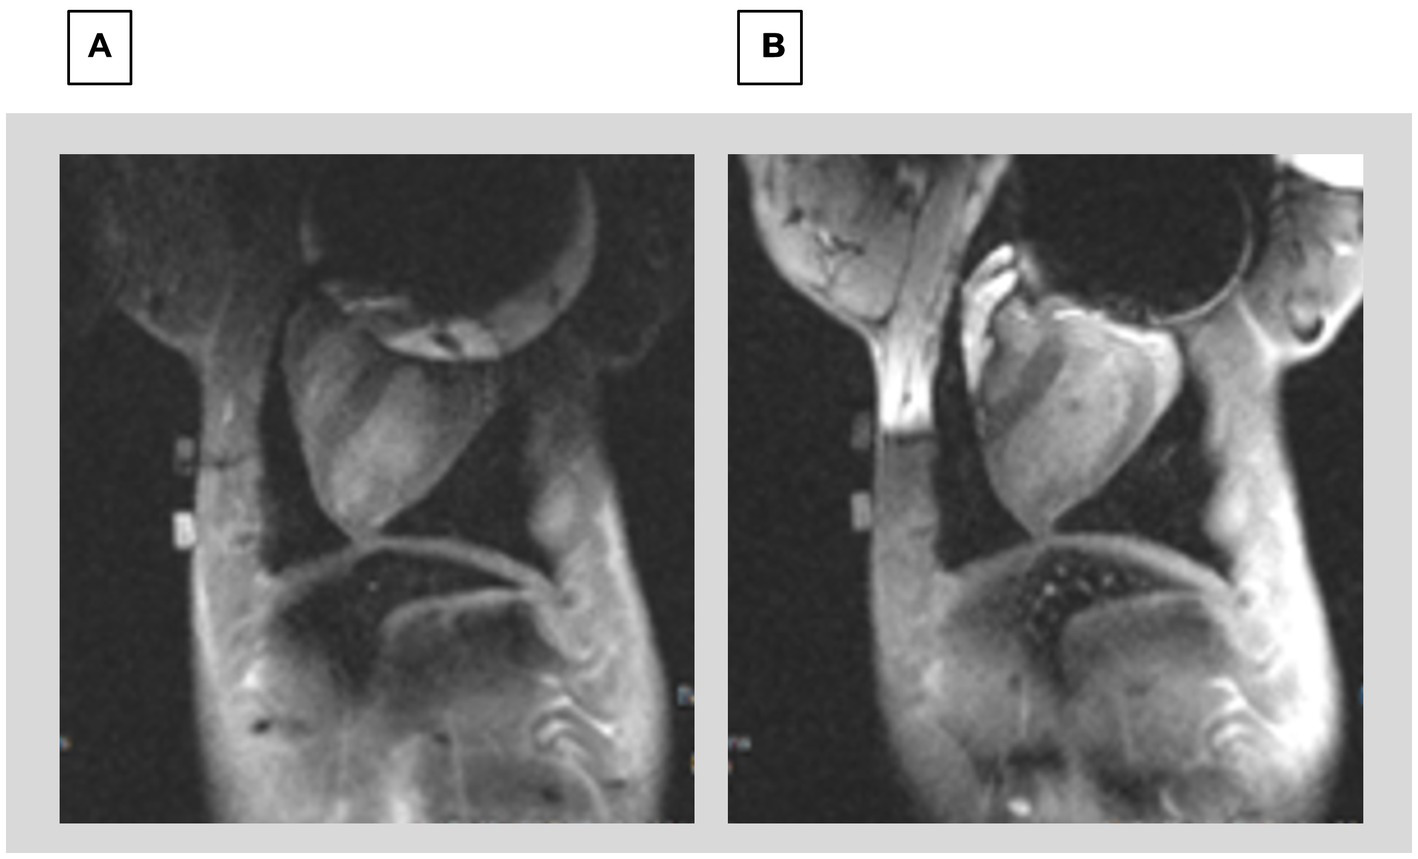

Swine breath-held ECG-gated 2D LGE scans were conducted to validate the ability to correct ICD-related artifacts. Once the shim coil location and current were optimized, it was possible to validate that the shim values were also correct for 2D LGE. Figure 9 compares 2D LGE images acquired before and after shimming.

Figure 9

Comparison of 2D LGE (A) prior to shimming and (B) after shimming using the CSS system. The image prior to shimming has severe distortions at the top of the Left ventricle, whereas the image after shimming allows visualizing the entire LV.

3D Navigated LGE imaging was performed in the swine using ECG-gating and prospective respiratory navigators. In Figure 10, images can be compared between before and after shimming. Since the scan times for 3D LGE were ~ 6 min, the 3D results demonstrate the temporal stability of the CSS system.

Figure 10

Navigated 3D LGE in sagittal and axial direction; prior to (A,C) and after (B,D) shim correction. Red arrows indicate location of artifacts. Note complete axial image in D.